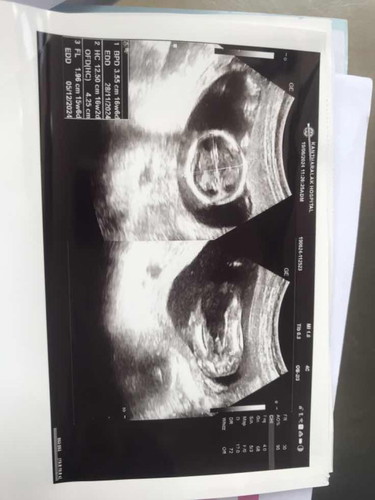

อายุครรภ์16w2d ค่ะ แต่ค่าที่อยู่ในใบซาวด์เหมือนเคลื่อนเลยค่ะ อยากรู้ว่าค่าที่ออกมาน้องตัวเล็กไหมคะ แล้วใช่ชายไหมคะ

อวัยวะเพศตั้งโด่เลยค่ะถึงน้องจะหนีบแต่ต้องรอดูนะคะเพราะว่าอาจมีเปลี่ยนแปลงได้